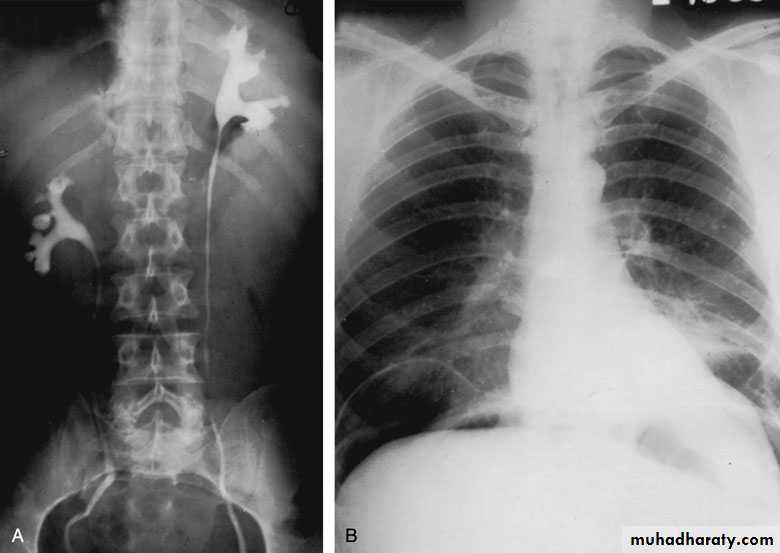

Horseshoe Kidney

found in 1:1000 necropsies an is commoner in men.

probably the most common of all renal fusion anomalies

The anomaly consists of two distinct renal masses lying

vertically on either side of the midline and connected at

their respective lower poles by a parenchymatous or fibrous

isthmus that crosses the midplane of the body.

Fusion of the renal masses early in embryonic life, so its ascent

will be impeded by inferior mesenteric artery.

The kidneys are low located, mal rotated and pelves lie anteriorly

Symptom When present, they are related to complications like hydronephrosis, infection, or calculus formation

Diagnosis ultrasound, IVU, CT scan